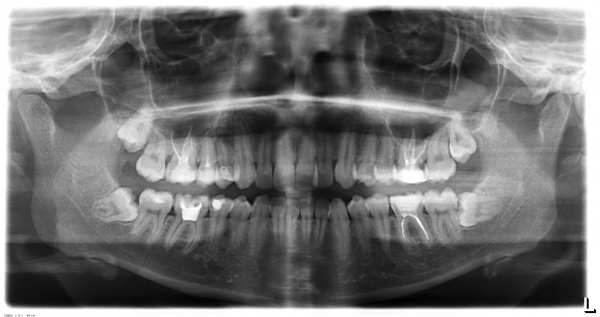

Увидеть зарождающуюся или уже сформированную кисту может только врач-стоматолог по рентген-снимку. Поэтому регулярные профилактические осмотры – не странная прихоть стоматологов, а реальная возможность своевременно начать лечение и спасти один или несколько зубов.

Зачастую наличие кисты зуба диагностируется случайным образом при проведении рентгенологического исследования (прицельного снимка зуба, ортопантомограммы, компьютерной томографии зубов).

Как уже отмечалось выше, диагноз кисты зуба подтверждается посредством рентгенологического исследования. На снимке отображается кистозная капсула, по очертаниям которой можно сделать вывод о размерах новообразования, степени поражения кости челюсти, состояние корня и корневых каналов.

10-летний мальчик был направлен в отделение челюстно-лицевой хирургии для оценки боли и отека в левом преддверии нижней челюсти.При физикальном обследовании обнаружено твердое подслизистое образование с расширением кортикальной пластинки в области второго премоляра. Панорамная рентгенограмма показала четко выраженное рентгенопрозрачное поражение размером примерно 3 × 2 см в диаметре, включая коронки 2-го левого премоляра нижней челюсти, не прорезавшегося. В поражение также были вовлечены корень соседнего клыка, 1-й премоляр и 1-й моляр. Корневые вершины этих зубов еще не закрылись. Признаков резорбции корня не было (). Учитывая возраст пациента и близость к нижней границе нижней челюсти, планировалась марсупиализация кистозной полости с сохранением всех пораженных зубов.Интраоперационно () из-за чрезмерной подвижности 2-го премоляра зуб не удалось сохранить. В послеоперационном периоде для предотвращения опрокидывания 1-го премоляра и моляра в дефект был установлен фиксатор пространства.

Ортопантомограмма (OPG) показала большое рентгенопрозрачное поражение с прорезыванием 2-го премоляра в левой части тела нижней челюсти

Случай 1 предоставляет информацию о скорости роста воспалительных зубных кист: за трехлетний период киста достигла диаметра 3 см (рис. 1а, б). Shear 1 рентгенологически показала, что зубные кисты диаметром 4–5 см могут развиться через 3–4 года.

При клиническом обследовании у пациентки остались все постоянные зубы и сохранен левый второй первичный моляр нижней челюсти. Рентгенологические записи включали ортопантомограмму, боковую цефалограмму, задне-переднюю цефалограмму и рентгенограмму запястья. Ортопантомограмма выявила четко выраженное рентгенопрозрачное поражение на левой стороне нижней челюсти, окружающее непрорезавшийся левый второй премоляр нижней челюсти, который, по-видимому, был наклонен мезиально ниже оставшегося первичного второго моляра.Корень соседнего премоляра был включен в поражение, но резорбции корня не наблюдалось (рисунки 1 и 2).

Послеоперационная ортопантомограмма (ОПГ), сделанная через 6 месяцев после операции, выявила отсутствие каких-либо рентгенопрозрачных поражений и успешное прорезывание второго левого премоляра нижней челюсти (рисунки 6 и 7).